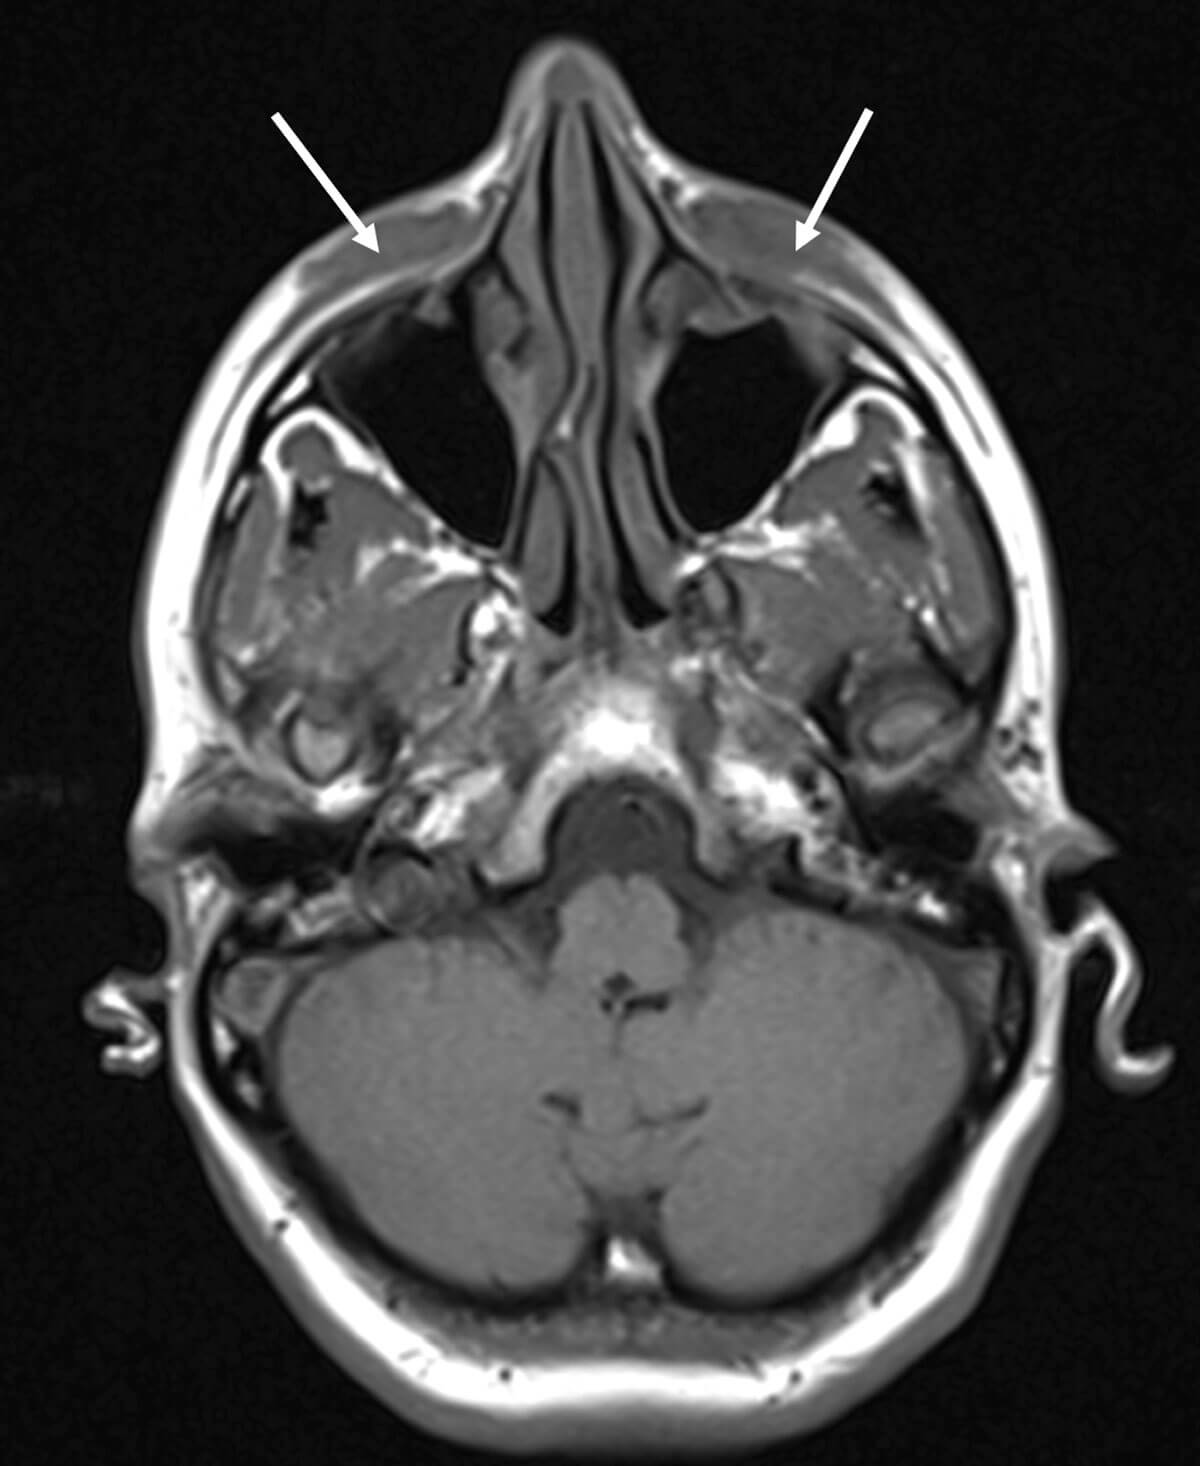

On physical examination, there were two rubbery soft tissue mass deposits on the inferior aspects of both eyes, extending superiorly to medial canthus. Nasal endoscopy revealed a 1cm ulceration in nasal septum, but no mucosal erythema or purulent discharge. Blood tests were ordered, including RAST total and specific IgE to rule out an allergic reaction and which came back as normal. A full vasculitis screen, including measurement of serum ACE, ANCA, auto antibody screen, MPO, PR3, ESR and CRP, was performed, which again all came back within the normal ranges. A chest x-ray did not show any cause for concern and her MRI scan of the orbits and soft tissues of the face confirmed diffuse soft tissue thickening which affected the infraorbital / premaxillary regions, extending to dermis to 12mm depth (AP) and 40mm (TR) (Figure 3). The conclusion from MRI initially was a differential diagnosis including lymphoma, IgG4 disease, sarcoid or Wegeners granulomatosis. She was subsequently listed for examination of the nose under general anaesthesia for septal biopsy +/- infra-orbital soft tissue biopsy.

Figure 3: MRI orbit and soft tissue face - diffuse soft tissue thickening which affected

the infraorbital / premaxillary regions, extending to dermis

extending to 12mm depth (AP) and 40mm (TR).